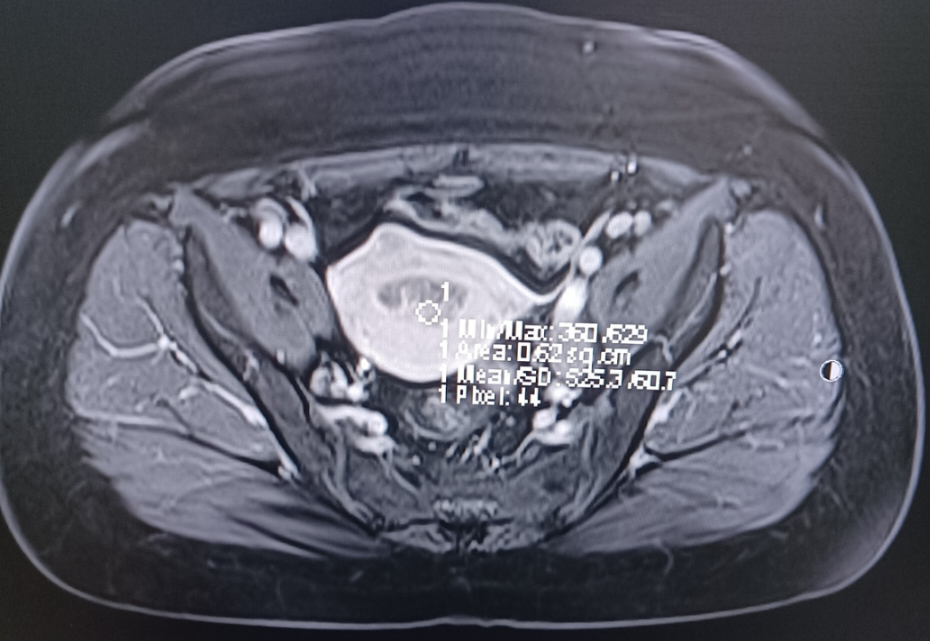

MRI: